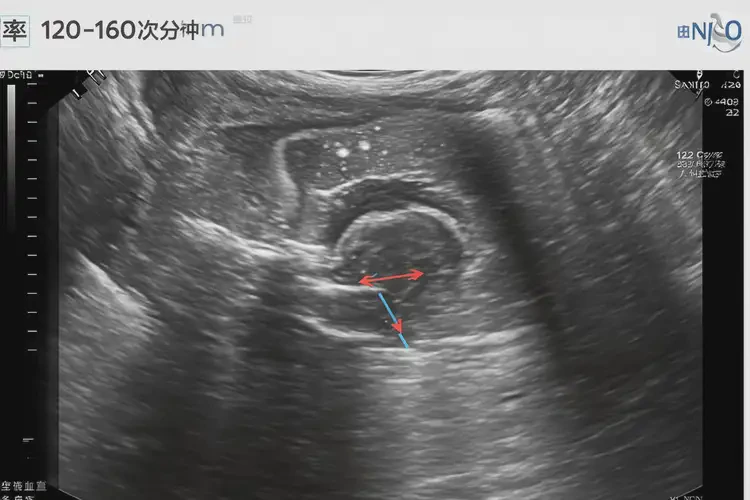

在懷孕第20周,胎兒的胎心率通常在120-160次/分鐘之間。胎心率低于120次/分鐘或高于160次/分鐘都可能表示存在潛在問題。胎心101次/分鐘明顯低于正常范圍,可能提示胎兒存在缺氧或其他健康問題。

懷孕第20周胎心101正常嗎(圖1)